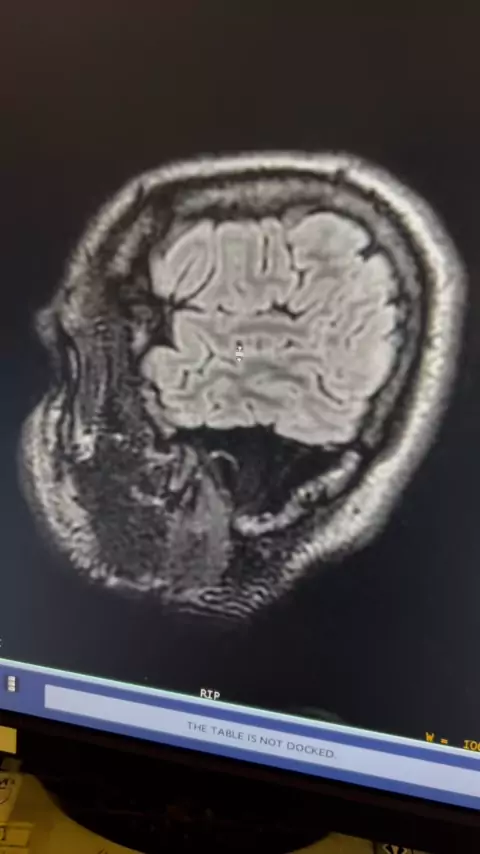

Paciente com epilepsia esquece de tomar remédio e tem convulsão durante o exame. # # # parati #